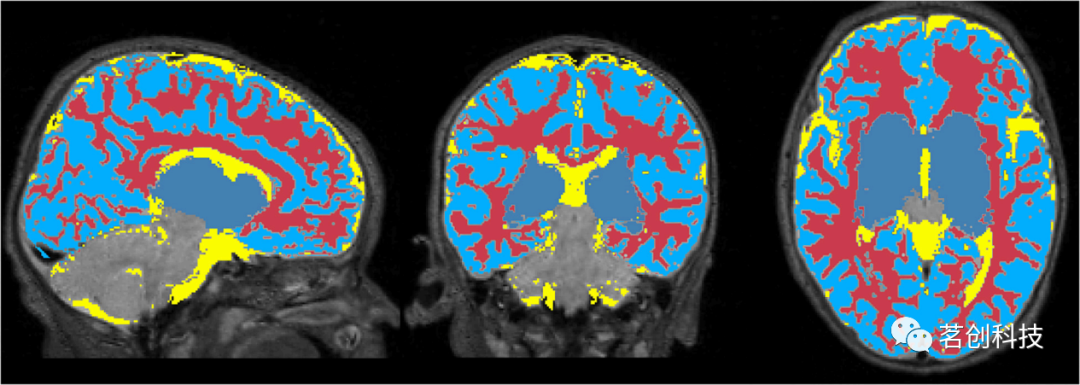

图6显示了NeoRS从Mantis组织概率图中创建的1mm各向同性二元掩膜。输出包含三个不同的二元文件,分别对应白质、SCF和GM。图7展示了用于混淆回归过程的3mm各向同性掩膜。

图6.从Mantis获得的组织概率图中创建的1mm各向同性掩膜。白质(红色)、脑脊液(黄色)、灰质(蓝色)。